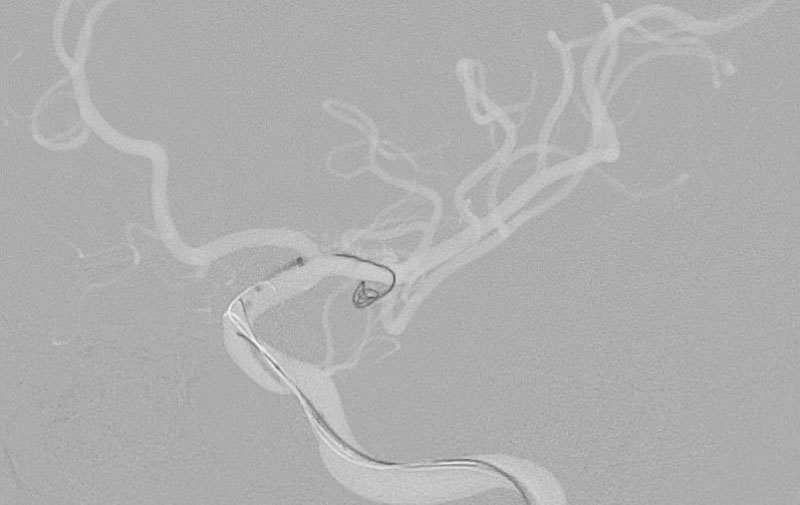

くも膜下出血

左中大脳動脈瘤破裂

40代

救急外来

No.1596 手術中